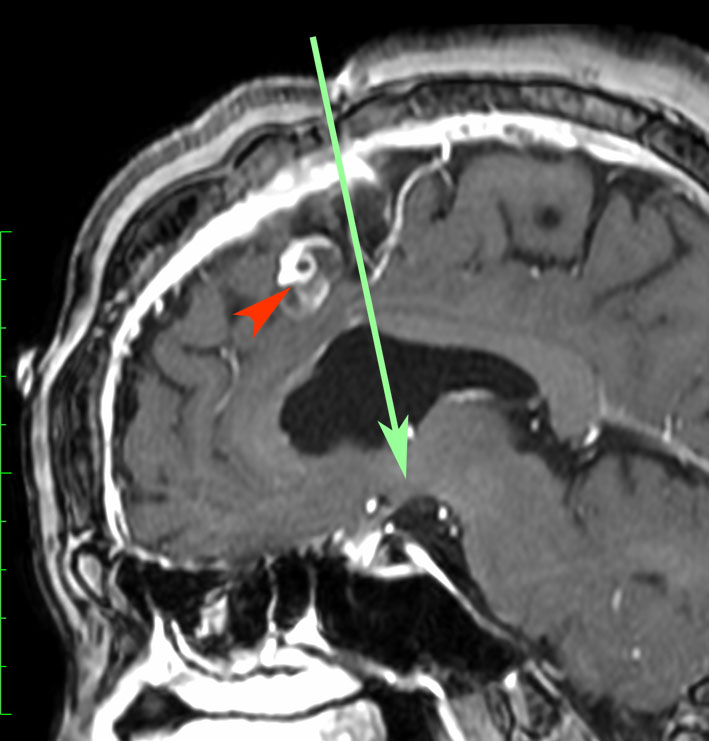

矢印の先に見えるように下垂体は正常の形態です。この画像から灰白隆起の左後方,乳頭体の前方が腫瘍発生母地ということがわかります。尿崩症もなく下垂体機能は正常です。経鼻的な内視鏡手術で腫瘍の大部分を摘出すれば下垂体機能は廃絶します。

とにかく失明を避けるために急いで経蝶形骨洞手術(transsphenoidal-transtuberculum sellae approach)で腫瘍のう胞の減圧をしました(緑の矢印の経路 by 函館中央病院加藤功先生)。その後に前頭開頭で腫瘍を全摘出しました(右側の画像)。尿崩症はでましたが下垂体前葉機能は正常です。

右視力 0.45,左明暗弁の視力が残りました。でももし,経鼻手術をしないでいきなり開頭すればおそらく全盲になっていた例です。